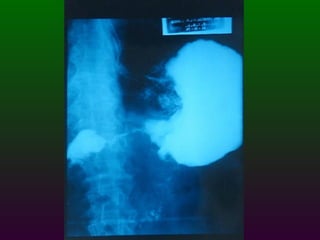

SEGD ENFERMEDADES DEL ESTÓMAGO Y DUODENO DIVISIÓN ANATÓMICA DEL ESTÒMAGO CARDIAS  FONDO CUERPO  ANTRO  PÍLORO

SEGD ENFERMEDADES DEL ESTOMAGO Y DUODENO El duodeno se divide en cuatro porciones; que se extienden desde el píloro hasta el ligamento de Treitz. La primera porción se denomina bulbo duodenal.

SEGD ENFERMEDADES DELESTOMAGO Y DUODENO El duodeno se divide en cuatro porciones; que se extienden desde el píloro hasta el ligamento de Treitz. La primera porción se denomina bulbo duodenal.